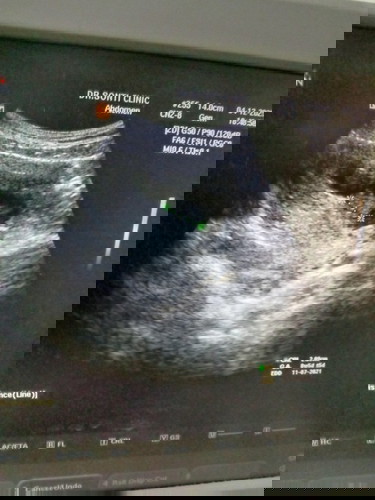

ท้องได้11+

ท้องได้ประมาณเกือบๆ3เดือนค่ะ แต่มีเลือดออกช่องคลอด คล้ายประจำเดือน ไม่มีปวดท้องอย่างใด อยากทราบว่าเกิดจากอะไรคะ แม่ๆคนไหนเคยเป็นบ้าง #ขอคำคิดเห็นหน่อยคะ

เคยค่ะ ตอน 3 เดือนเหมือนกันค่ะ แต่ไปหาหมอทันที คุณหมอแจ้งว่า เป็นเลือกที่ตกค้าง แต่ก็U/S ว่าเสียงหัวใจปกติไหม ตรวจภายในว่าปากมดลูกเป็นยังไงบ้าง และให้ยามาทาน 7 วัน ถ้ายาหมดแล้ว ยังไม่หายให้ไปหาหมอใหม่ แต่แพทย์ก็ลงความเห็นว่า แท้งคุกคาม นะคะ

เราเป็นอยู่มีเลือดสดสีแดงเข้มออก ไปรพ.หมอจะให้นอน admit สังเกตุอาการพร้อม u/s ว่าหัวใจลูกน้อยยังเต้นอยู่ไหม และตรวจช่องคลอดว่าปากมดลูกเปิดรึป่าว พร้อมฉีดยากันแท้งค่ะ ของเราโชคดีน้องยังแข็งแรง หัวใจเต้นอยู่ค่ะ #แนะนำรีบไปด่วนนะค่ะ

เป็นค่ะ ช่วง12สัปดาห์ หมอซาวดูเด็กปกติ ฉีดยากันแท้ง รอ1สัปดาห์ ไปตรวจพบสาเหตุมาจาก รกปิดช่องคลอดมดลูกขยายตัว ถ้ารกดันขึ้นด้อปกติค่ะ ตอนนี้ น่าจะดันขึ้น รอ14นี้ไปตรวจอีกทีค่ะ อย่ากังวลนะคะ